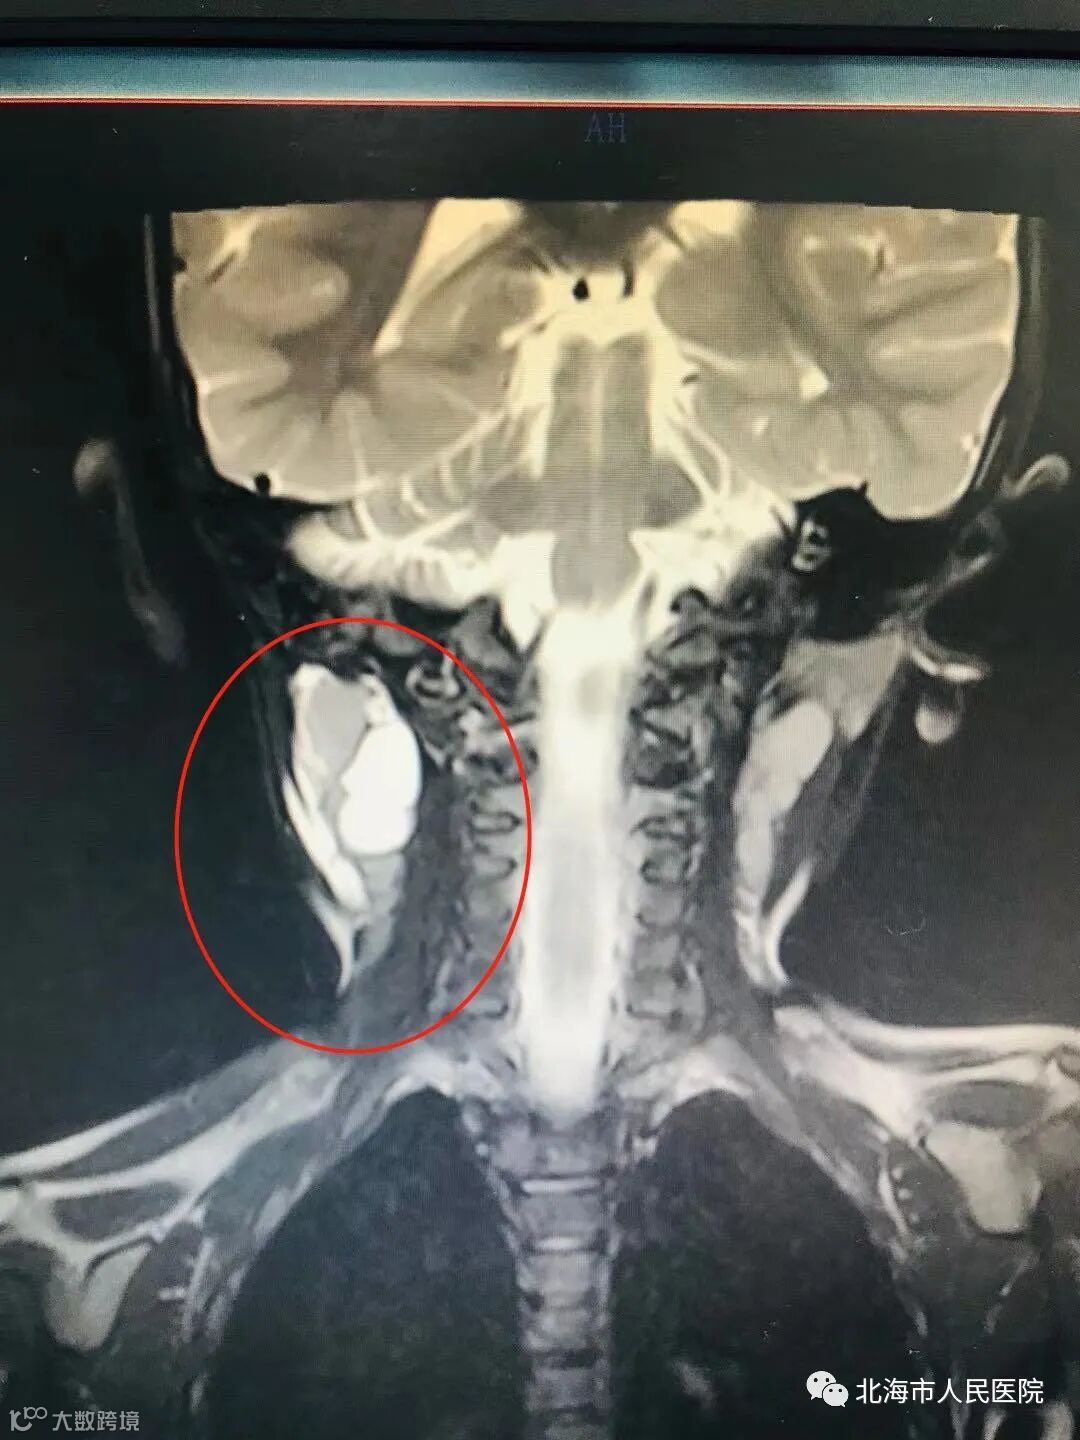

于是在上个月31日,小梅被收治入院,为了降低手术的风险,又进行了详细的增强磁共振的检查,排除了其他病变后,1月6日上午,耳鼻咽喉科副主任 副主任医师 叶小武、肖静主治医师、林鸿健医师、韦夏媛医师组成的四人小组开始对小梅进行手术。

在手术中发现三个囊肿,最大的囊肿有4cm*2.5cm大,从下颌一直延伸至颅底,囊肿在颈鞘内九曲十八弯,包裹了副神经和颈从神经,贴进颈总动脉,其中,副神经是支配人体肩部活动的,稍不小心,就可能会造成手臂的瘫痪,颈总动脉又支配着人的颅脑,可想手术的复杂程度。在巨大的压力之下,凭借精湛的技术及过硬的解剖知识,四人小组通力合作,一丝不苟、小心翼翼地操作着,历时两个多小时,终于取出了小梅颈部的囊肿。目前,小梅正在观察阶段,不久便可以出院。